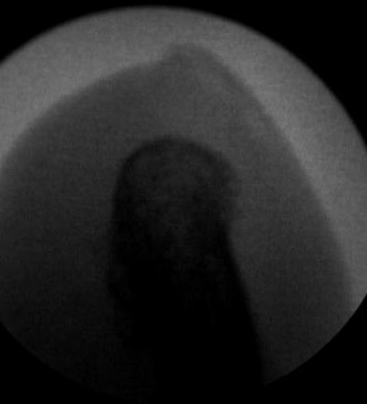

Ante un cambio en la forma y coloración de la uñas, lo primero que pensamos es que puedan ser «hongos» pero en la gran mayoría de los casos el problema está «en el interior». La uña está engrosada, puede tener alguna grieta, cambio de color y además puede ser dolorosa a la presión del calzado. Ese aspecto de «uña fea» puede ser a consecuencia de la malformación o del mal crecimiento del hueso que hay en el interior del dedo y que da lugar a esta malformación de la uña debido a que este hueso invade el territorio de todo el aparato ungueal. Digamos que la uña en vez de crecer normalmente a lo largo (longitudinalmente) crece a lo alto (verticalmente) dando ese aspecto de «uña enferma». Por ello, para un buen diagnóstico es necesario un estudio radiológico donde poder observar esa excrecencia de hueso que dará lugar a ese mal crecimiento de la uña. Las imágenes radiológicas nos van a mostrar ese montículo en el hueso causante de la deformidad de la uña.